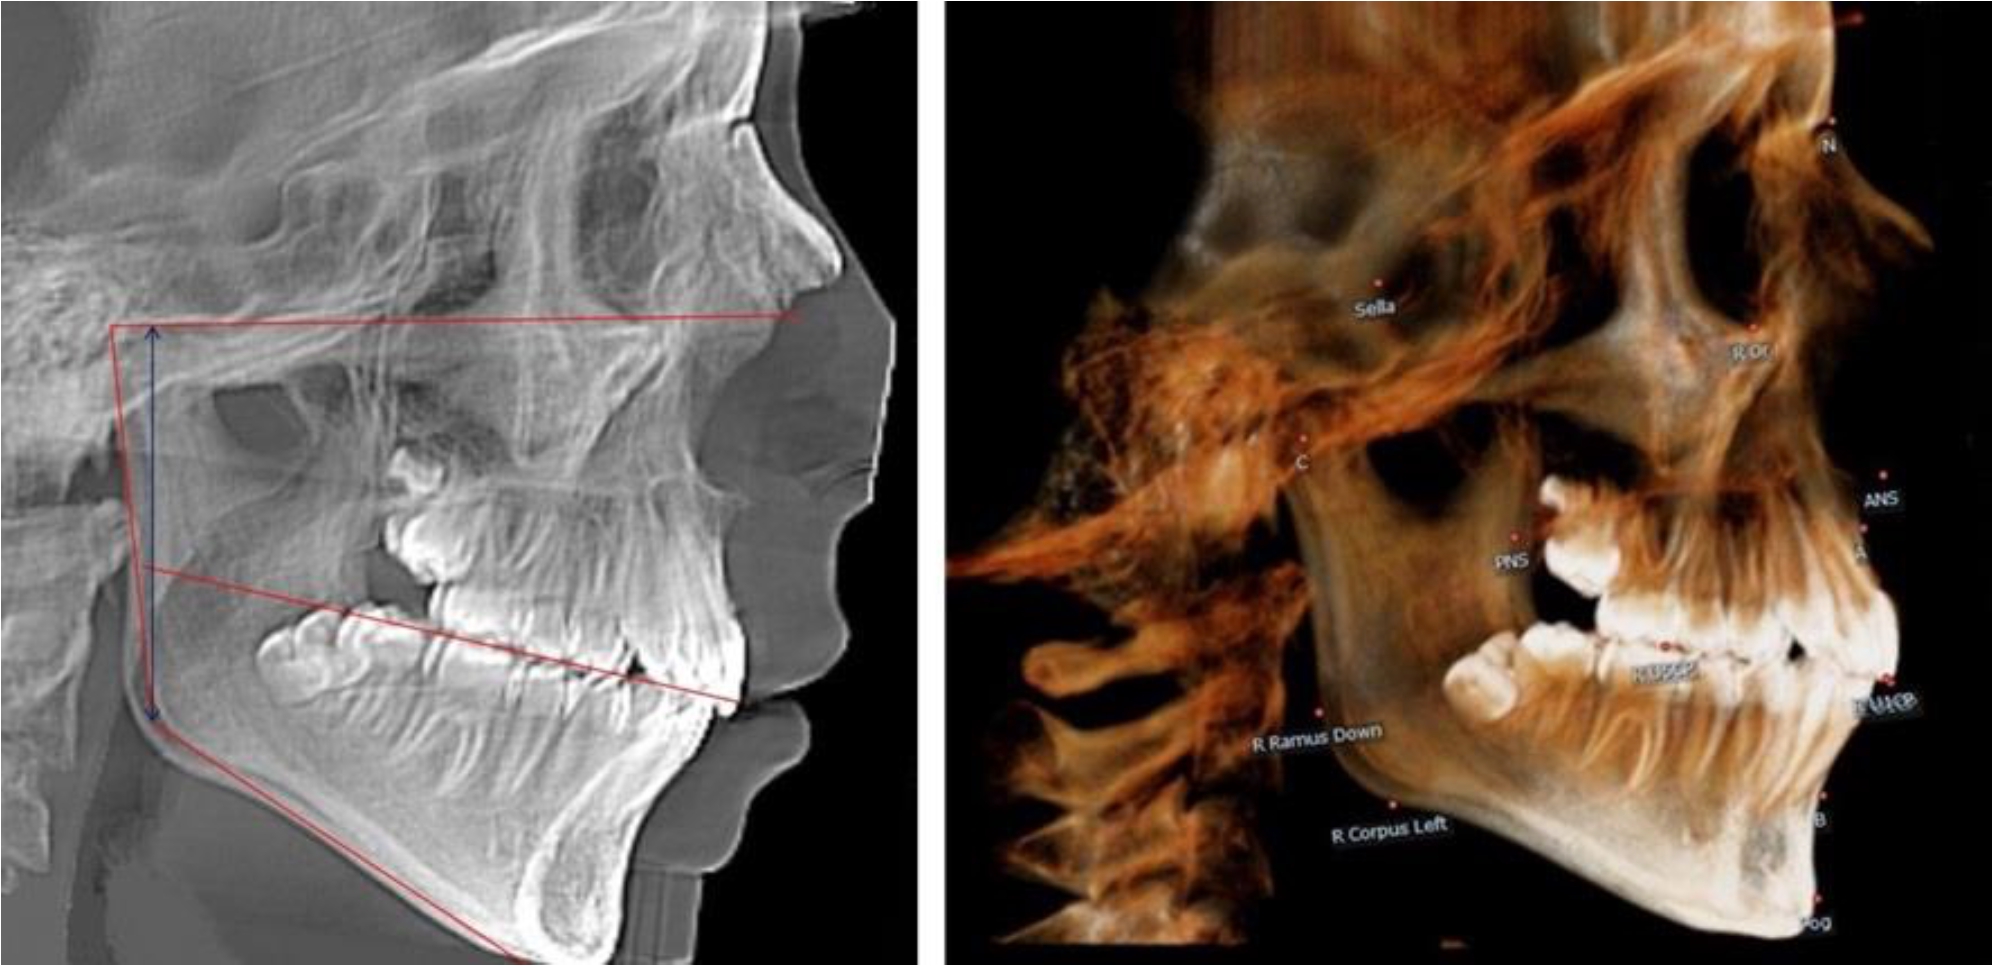

На боковых телерентгенгенограммах вершину суставной головки обозначали точкой кондиион Cond. Касательные линии к ветви и телу нижней челюсти пересекались в точке, которую обозначили Go. Точкой hPOcP обозначали дистальный бугорок нижнего второго моляра вблизи окклюзионного контура коронки. Указанный ориентир соединяли с межрезцовой точкой при построении окклюзионной линии. Высота ветви определялась расстоянием Go-Cond. Окклюзионная линия служила границей между верхней (окклюзионно-суставной) линией и нижней (окклюзионно-альвеолярной) линией.

На ортопантомограмме точки Cond соединяли между собой суставной линией Cond-Cond. Касательная к ветви нижней челюсти соединяла выступающие точки, которые соединялись в области угла и определяли положение точки гонион Go с обеих сторон, которые соединяли гониональной линией Go-Go.

Горизонтальная линя, соединяющая окклюзионные точки hPOcP, определялась как окклюзионная горизонталь.

В 1-й группе были проанализированы 7 телерентгенограмм и 7 ортопантомограмм, что составило (6,60 ± 2,41) % от числа изученных рентгенограмм. На всех парах рентгенограмм угол нижней челюсти, измеренный на телерентгенограмме, соответствовал углу, полученному при построении угла на ортопантомограмме. Окклюзионная линия практически однотипно делила ветвь на два отдела (рис. 1).

Как на ортопантомограмме, так и на телерентгенограмме высота ветви у детей в периоде сформированного прикуса молочных зубов составляла (42,21 ± 2,48) мм. При этом высота верхней окклюзионно-суставной части была (22,57 ± 1,46) мм, а нижней – (19,64 ± 1,54) мм.

Учитывая вариабельность абсолютных величин, определи относительные показатели соразмерности частей ветви нижней челюсти. Так, отношение высоты верхней части ветви к нижней в среднем составляло 1,15 ± 0,13. Отношение общей высоты ветви к верхней ее части составляло 1,87 ± 0,14, а отношение общей высоты ветви к нижней ее части было 2,14 ± 0,16 и достоверных различий по относительному показателю отношения всей высоты к верхней и нижней челюсти нами не отмечено (р ˃ 0,05). При этом визуально обе части выглядели примерно равноразмерными.

Рис. 1. ТРГ и ОПТГ пациента 1-й группы